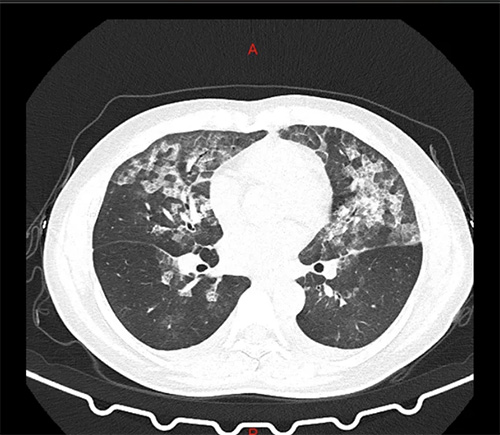

近日,河南郑州的张女士和王女士到医院就诊,结果胸部CT显示呈毛玻璃状,和新冠肺炎的CT表现基本一模一样。经询问,两人每天定时在家里喷洒高浓度的84消毒液,从而引起过敏性肺泡炎。主治医生李凤芝说:“张女士和王女士她们两个都是以头晕、乏力、闷气入院的,在疫情期间,常规查了胸部CT,结果显示呈毛玻璃状。”

↑↑张女士肺部CT

李凤芝还称,从CT影像来看非常像新冠肺炎,但是病人的接触史、症状表现,包括血象也是不符合的。

主治医生张小红主任称,张女士和王女士在家里使用84消毒液,确定是一个过敏性肺泡炎!

据了解,过敏性肺泡炎是指易感人群反复吸入各种具有抗原性的有机粉尘、低分子量化学物质,引起的一组弥漫性间质性肉芽肿性肺病。反复发作可致肺纤维化,甚至可发展为呼吸衰竭。